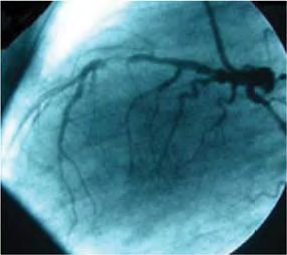

Um paciente com história de dor torácica aos esforços comparece à consulta por estar mais cansado do que o normal. Refere que vem apresentando ortopneia e dispneia paroxística noturna. Foram realizados investigação laboratorial, Holter, ecocardiograma e cateterismo cardíaco. O ecocardiograma e o cateterismo estão representados a seguir.

Acervo Pessoal

Tendo em vista esse caso clínico, as imagens apresentadas e os conhecimentos médicos correlatos, julgue os itens a seguir.

Na imagem do cateterismo, observa-se lesão em artéria descendente anterior.